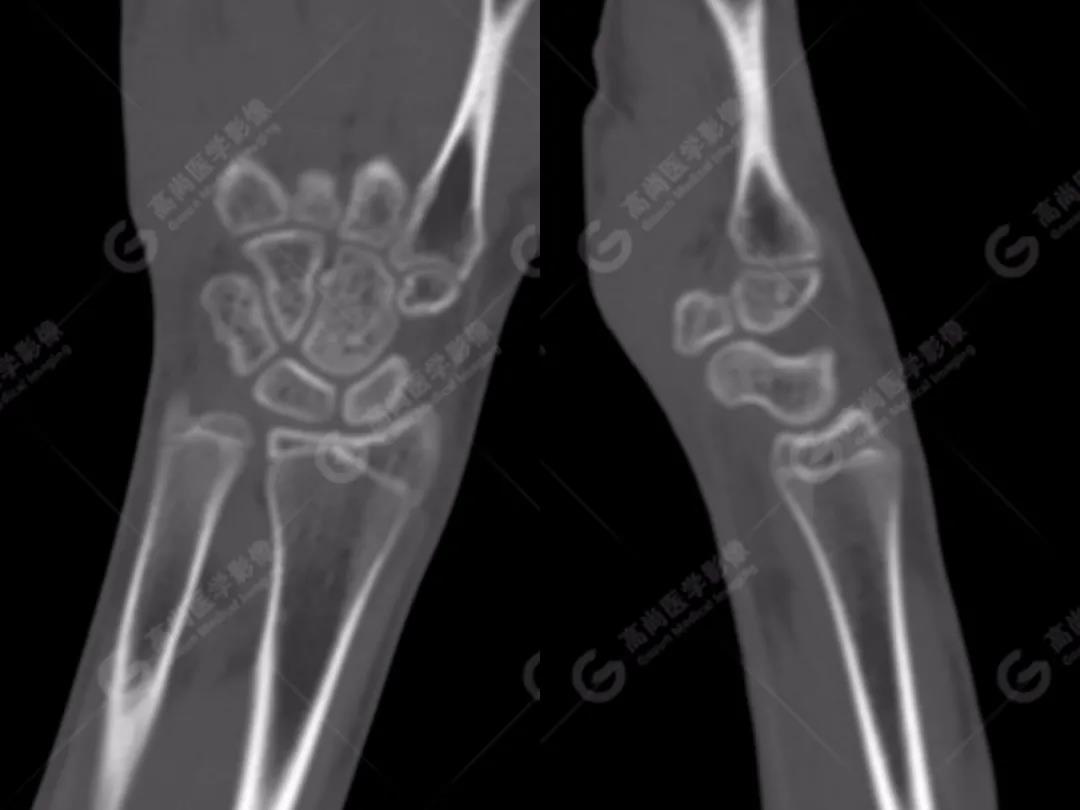

2、常規(guī)CT圖像

常規(guī)CT平掃灰階圖像上雙腕關(guān)節(jié)仍然未見明顯骨折征象。

3、雙能CT骨髓成像(雙能虛擬去鈣圖像)

高尚醫(yī)學(xué)影像診斷中心的Flash雙源CT可以利用雙能量骨髓成像來(lái)顯示骨骼內(nèi)的骨髓水腫,而外傷性的骨髓水腫往往提示骨挫傷或小梁微骨折。重建一下雙能虛擬去鈣骨髓圖像,進(jìn)一步排除骨挫傷、微骨折。

雙能CT骨髓成像圖上發(fā)現(xiàn)了左側(cè)橈骨遠(yuǎn)端和右側(cè)舟狀骨骨髓水腫(箭頭所示),進(jìn)一步查體這兩處骨髓水腫剛好與患者的局部壓痛點(diǎn)相一致。